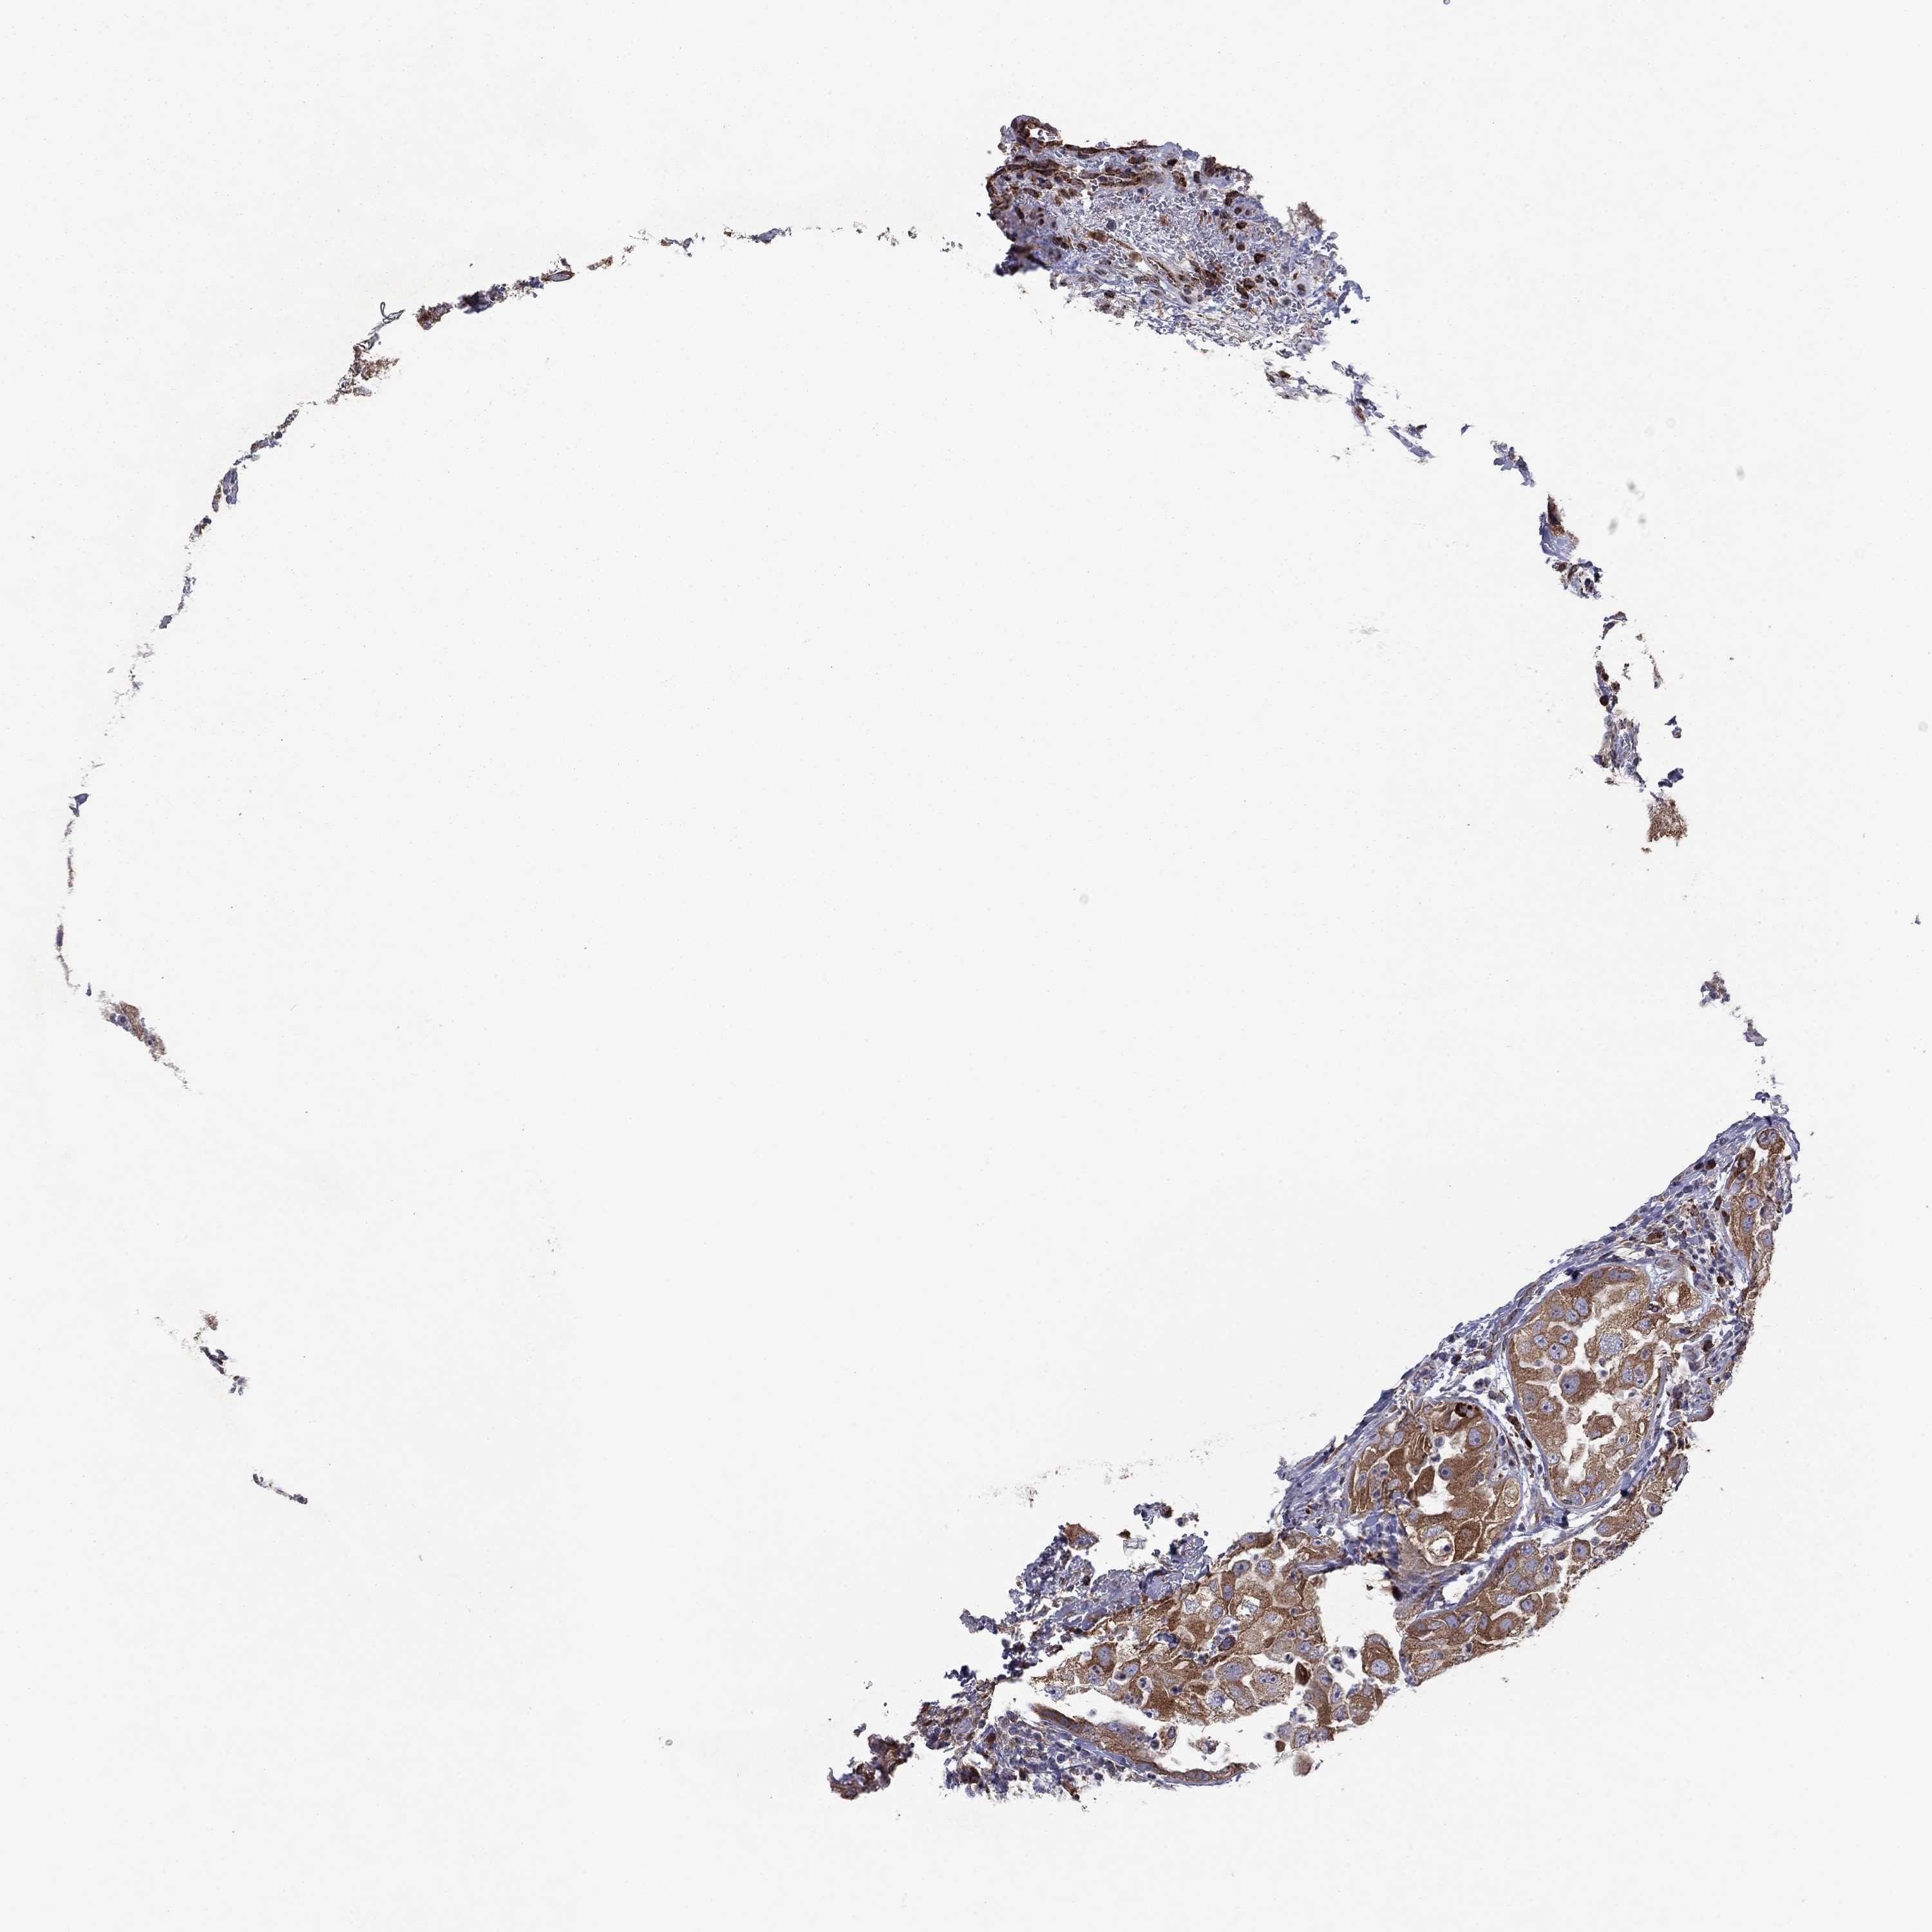

UROTHELIAL CANCER - Protein expressioni

A mouse-over function shows sample information and annotation data. Click on an image to view it in a full screen mode. Samples can be filtered based on level of antibody staining by selecting one or several of the following categories: high, medium, low and not detected. The assay and annotation is described here.

Note that samples used for immunohistochemistry by the Human Protein Atlas do not correspond to samples in the TCGA dataset.

Antibody stainingi

Antibody staining in the annotated cell types in the current human tissue is reported as not detected, low, medium, or high, based on conventional immunohistochemistry profiling in selected tissues. This score is based on the combination of the staining intensity and fraction of stained cells.

Each image is clickable and will lead to virtual microscopy that enables deeper exploration of all samples and also displays staining intensity scores, fraction scores and subcellular localization as well as patient and tissue information for each sample.

Antibody HPA076194

Staining

High

Medium

Low

Not detected

Intensity

Strong

Moderate

Weak

Negative

Quantity

>75%

75%-25%

<25%

None

Location

Nuclear

Cytoplasmic/membranous

Cytoplasmic/membranous,nuclear

Urothelial carcinoma, High grade

Urothelial carcinoma, Low grade